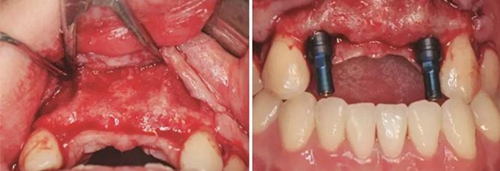

圖13 取出鈦釘后 圖14 攜帶體示植體位置方向良好

圖15 種植術(shù)后 圖16 種植后嚴(yán)密縫合創(chuàng)口

圖17 CBCT測量骨量變化 圖18 早期修復(fù)戴牙當(dāng)天